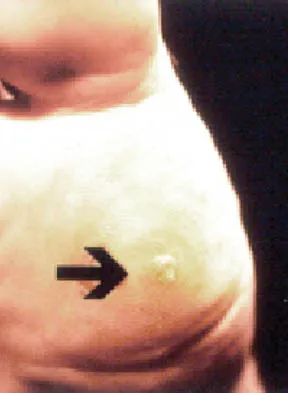

Figure 3 shows the clinical photograph of a wrestler who has an acute mass in his ear. He does not wear protective headgear. The area is mildly tender and without erythema. Management should consist of

Explanation

The patient has an auricular hematoma. This injury is typically related to blunt trauma, occuring in wrestlers who do not use protective headgear. The goal of treatment is to remove the fluid, reapproximate the perichondrium to the underlying articular cartilage, and limit reaccumulation of the fluid in attempt to prevent cartilage necrosis. Aspiration and application of a compressive dressing offers the best chance to achieve this goal. There are no signs of infection such as marked tenderness, erythema, or surrounding edema to justify antibiotic use or irrigation and debridement. The mass does not warrant excision. Kaufman BR, Heckler FR: Sports-related facial injuries. Clin Sports Med 1997;16:543-562.